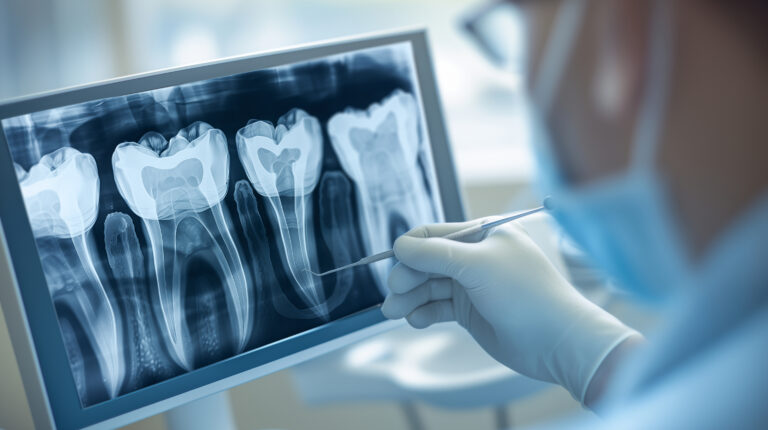

Leczenie kanałowe jest jedną z najczęściej wykonywanych procedur w gabinetach stomatologicznych. Procedura ta polega na usunięciu zakażonej lub uszkodzonej miazgi z wnętrza zęba, a następnie wypełnieniu powstałej przestrzeni specjalnym materiałem. Leczenie kanałowe pozwala uratować ząb, który w przeciwnym razie musiałby…